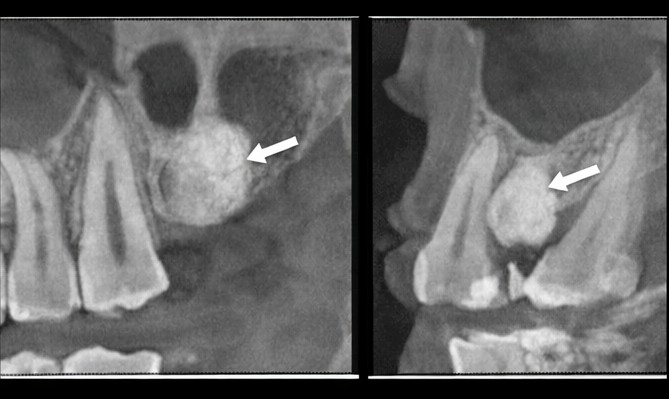

To further characterize the bony lesion, a cone-beam computed tomography (CBCT) scan was obtained. The CBCT confirmed an exophytic bony outgrowth arising from the buccal cortical plate, extending into the overlying gingival soft tissues (Figure images not included). The trabecular pattern and continuity with the cortical bone were consistent with a benign osseous growth.

The radiographic findings, along with clinical examination, supported gingival exostosis as the most likely diagnosis.